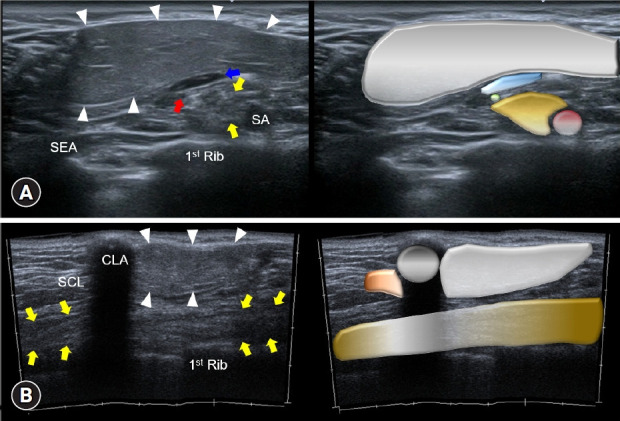

Ultrasound assessment of a supraclavicular lipoma entrapping the brachial plexus: a diagnostic insight.